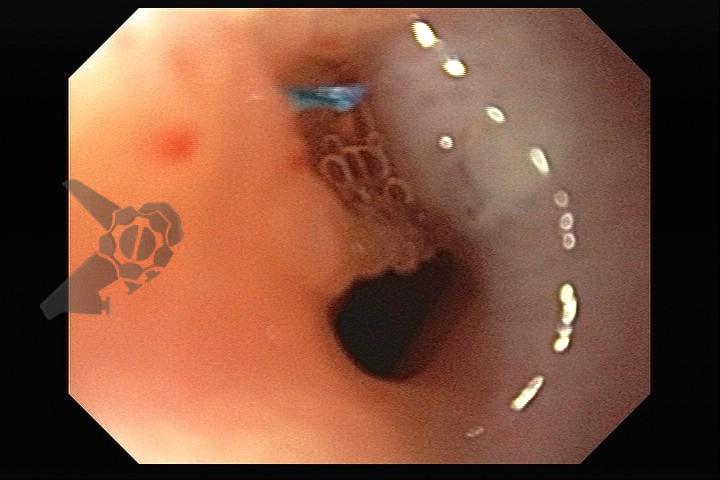

Esôfago de Barrett e Vigilância Endoscópica: o que as diretrizes recomendam e o que o BOSS Trial revela

O esôfago de Barrett constitui a principal lesão precursora desse tipo de neoplasia, razão pela qual múltiplas sociedades médicas recomendam a vigilância endoscópica periódica como estratégia para detecção precoce de displasia e câncer inicial. Entretanto, as evidências que embasam a vigilância endoscópica em pacientes com esôfago de Barrett, em especial no que se refere ao intervalo ideal entre os exames, permanecem limitadas já que a maioria vem de estudos observacionais. Estudos populacionais indicam risco anual relativamente baixo de progressão para adenocarcinoma, variando de 0,12% a 0,22%¹. Portanto, atualmente, a qualidade da evidência que sustenta a vigilância endoscópica é muito baixa.

O estudo BOSS foi o primeiro ensaio clínico randomizado e o maior já realizado sobre vigilância endoscópica no esôfago de Barrett. Foi um estudo multicêntrico aberto realizado no Reino Unido com 3452 pacientes randomizados e mais de 39.500 anos-paciente de seguimento. O objetivo foi comparar duas estratégias: endoscopia programada a cada 2 anos versus endoscopia apenas em caso de sintomas ou necessidade clínica.